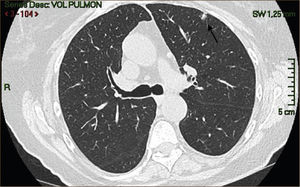

La masificación de los métodos de diagnóstico por imágenes, especialmente del TAC de Tórax, ha significado un importante aumento en la detección de NP pequeños, menores de 2cm, no visibles en la radiografía de tórax. Estos nódulos pueden ser tanto sólidos como sub-sólidos, cada uno tiene diferente comportamiento, velocidad de crecimiento y probabilidad de malignidad2,3 (Figuras 2 y 3).

Un nódulo pulmonar corresponde por tanto a tumores Etapa I (T1a o T1b). Estas lesiones especialmente las menores de 2cms no son visibles a la Radiografía de Tórax siendo sólo pesquisables mediante TAC, especialmente cuando son subsólidas.

El diagnóstico por imágenes mediante TAC de Tórax, cumple por tanto un rol fundamental en la identificación y caracterización de los nódulos pulmonares. Los cánceres pulmonares iniciales pueden presentarse como nódulos de diferente densidad: sólidos, cavitados, en vidrio esmerilado (VE: definidas como una intensidad discretamente mayor a la del parénquima pulmonar a través de la cual la vasculatura pulmonar es visible) o lesiones mixtas con componente sólido y VE. Figuras 2 y 33. En etapas más avanzadas los CPNCP se presentan como nódulos de mayor tamaño o masas (>3cms), sin embargo también pueden presentarse como lesiones consolidadas mal definidas, especialmente algunos adenocarcinomas productores de mucina. Estas lesiones pueden ser indistinguibles de una neumonía, pero a diferencia de estas persisten en el tiempo pese al tratamiento antibiótico 27,28.

Actualmente la densidad del nódulo es uno de los aspectos más importantes a considerar en el estudio de los NP. Los nódulos sólidos tienen un riesgo de malignidad general de 7%, y como se mencionó previamente, mientras mayor sea el tamaño del nódulo mayor es el riesgo51.

Las lesiones Subsólidas tienen un mayor riesgo de malignidad que puede alcanzar un 18%51. Las lesiones subsólidas pueden corresponder a lesiones en Vidrio Esmerilado Puro (VE o GGO: Ground Glass Opacity) o a lesiones mixtas con un componente en VE y una zona sólida (Figuras 4, 5 y 6).

Nódulos sólidos menores a 4mm sólo requieren un seguimiento en 12 meses, en cambio nódulos mayores de 8mm requieren un nuevo TAC en 3 meses o un TAC con contraste (para ver el refuerzo en UH), PET/CT o biopsia. Los nódulos de tamaño intermedio requieren seguimiento a diferentes intervalos. Si un nódulo sólido permanece estable por un período de 2 años se considera benigno4–7,39,49,50,54,63.

Las lesiones en VE corresponden en mucho casos a lesiones inflamatorias por lo que se recomienda un TAC inicial a los 3 meses, en este primer control ceca del 75% de estas lesiones desaparece. Las lesiones en VE que persisten corresponden como se mencionó generalmente a HAA o Adenocarcinoma in situ, los que tienen tiempos de duplicación prolongados. Se requiere por tanto seguimiento anual al menos por 3 años para determinar que no progresan. Las lesiones de mayor tamaño (>10mm) o que crecen o desarrollan un componente sólido durante el seguimiento deben ser biopsiadas3–7,48–50,53–57.